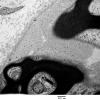

PERIPHERAL NEUROPATHY

16 DIABETIC NEUROPATHY

1 Symmetrical Sensorimotor Neuropathy (3)